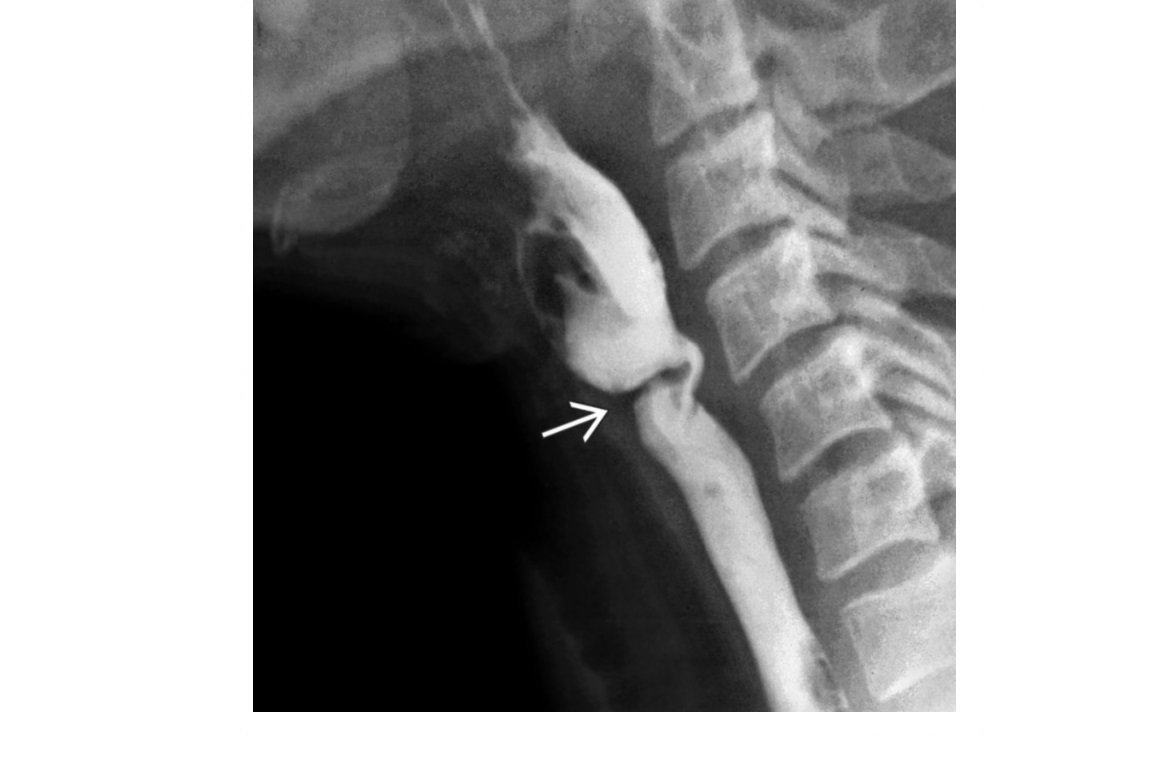

Zenker Diverticulum

Outpouching with rounded contour posteriorly in the neck is above the cricopharyngeus muscle

In hypopharynx!!!

Site of weakness is the Killian dehiscence - between the inferior pharyngeal constrictor muscle and cricopharyngeal muscle